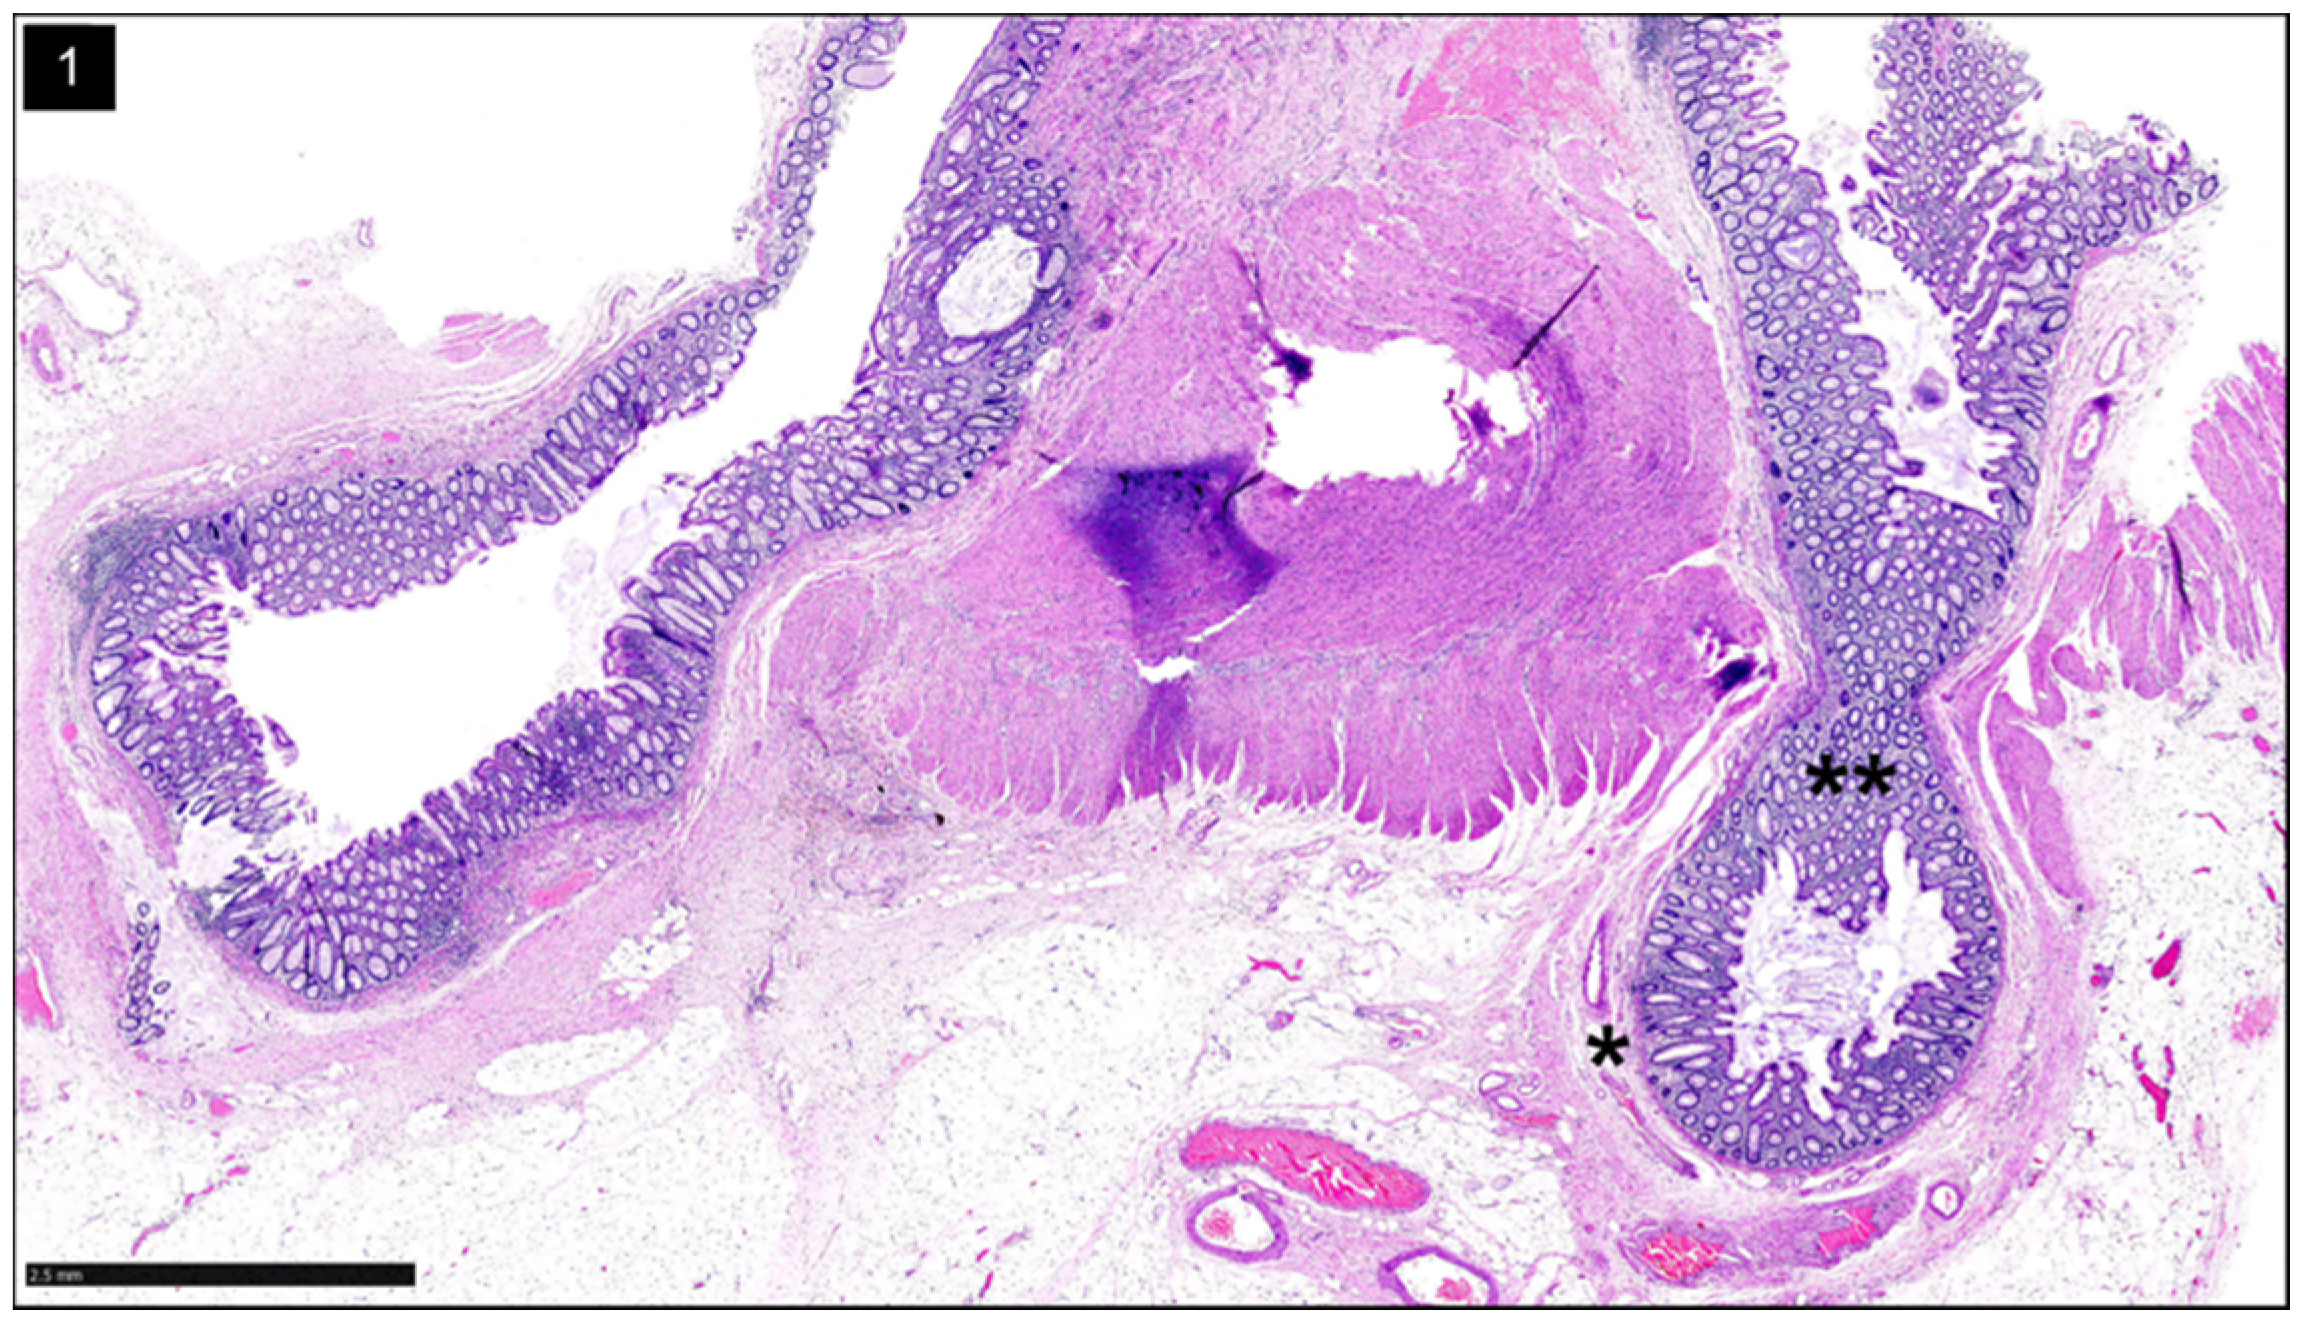

Histologically, diverticulitis shows inflammation of the diverticular pouch with or without mucosal ulceration. When the diverticular pouch is ruptured, subserosal abscess can form (Figure 3). Computed Tomography (CT) with intravenous (IV) contrast is the imaging modality of choice to evaluate for acute diverticulitis and its complications [27].

Figure 3.

Diverticulitis: H&E stain shows a diverticulum (circle) with acute inflammation and abscess formation in the peri colonic adipose tissue in the sigmoid colon (H&E, ×25).